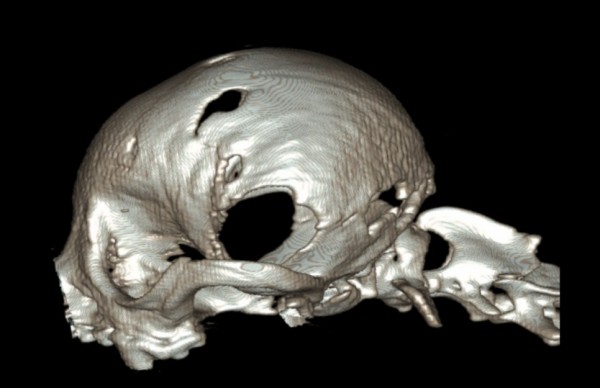

- 다수의 두개골 결손(calvarial defects) 도 관찰되었으나, 뇌 탈출은 없는 상태

3. Occipital Dysplasia & AOO → 후두골 및 경추 기형

5. 두개골 결손(calvarial defects)